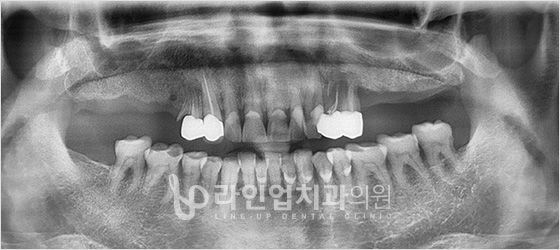

치료전 Before

치료후 After

下臼齿种植牙